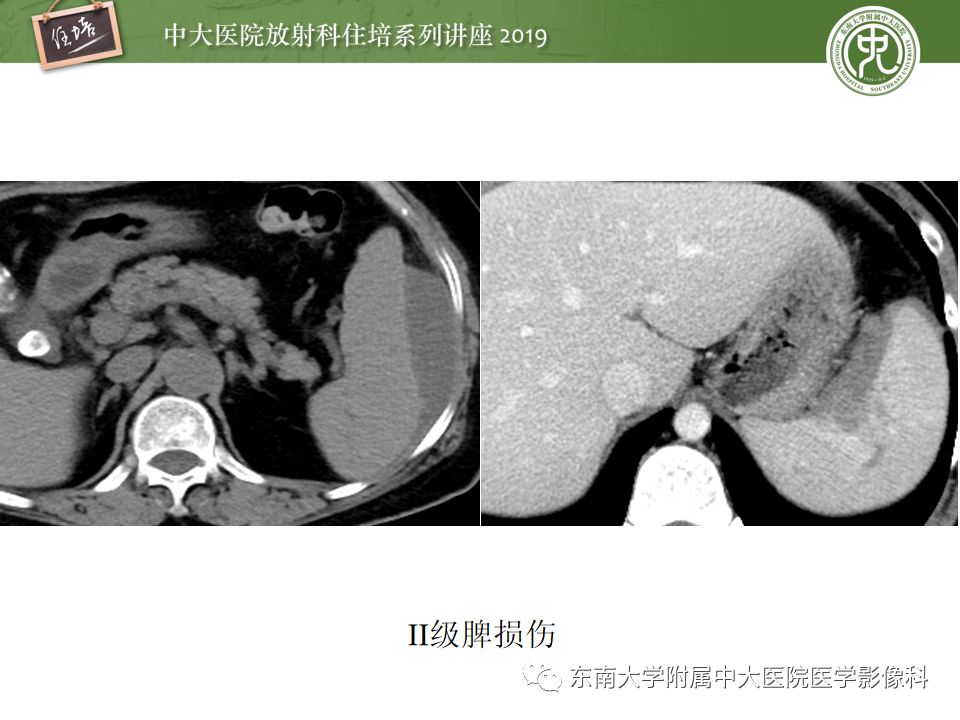

腹腔实性脏器钝性外伤影像诊断